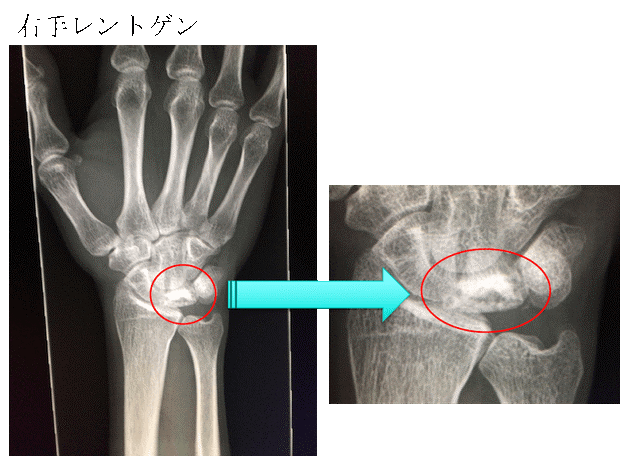

手首がいたい、手首の小指側が痛い、手首を曲げると痛い、尺骨突き上げ症候群。

TFCC損傷尺骨突き上げ症候群druj不安定症入院手術尺骨短縮術ギプス手術跡レントゲン入院記録抜釘手術。

TFCC損傷の原因となる尺骨突き上げ症候群とは。

尺骨突き上げ症候群S-HANDクリニック 埼玉県さいたま市 手外科。

尺骨突き上げ症候群手の治療専門サイト。

尺骨突き上げ症候群長野整形外科クリニック。